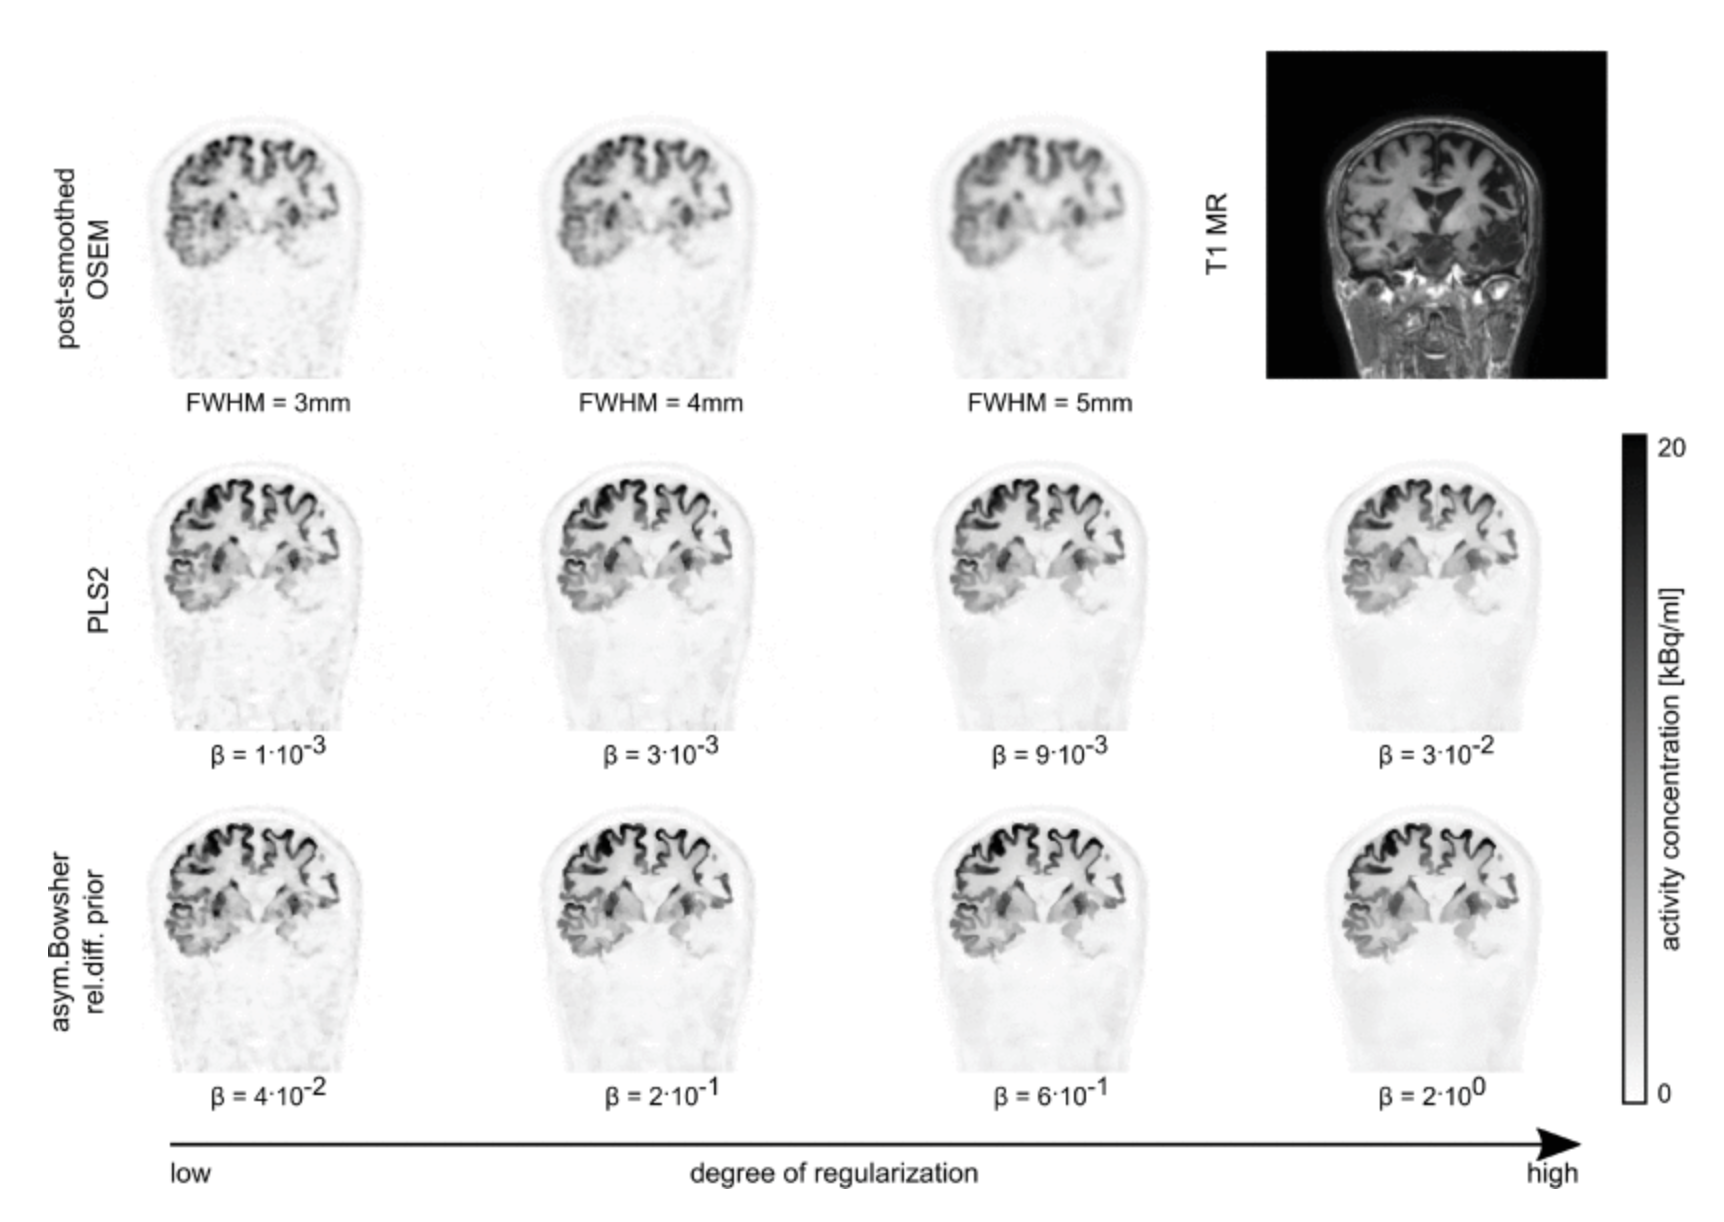

1. pls.png

Evaluation of parallel level sets and Bowsher’s method as segmentation-free anatomical priors for time-of-flight PET reconstruction

Georg Schramm, Martin Holler, Ahmadreza Rezaei, and 5 more authors

IEEE transactions on medical imaging, 2017